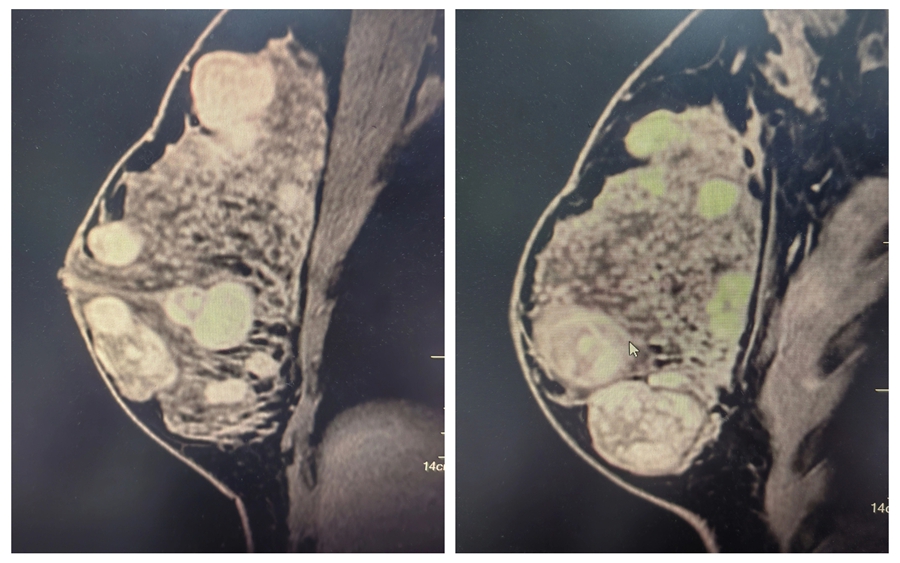

患者晓莉(化名)因自觉双侧乳房“疙疙瘩瘩”前来就诊,乳腺超声检查令人心头一紧,双侧乳房都长了结节,右侧乳腺更多,部分小结节融合成大结节,最大的直径达 5 厘米。

△乳腺核磁共振检查可见多结节分布

追溯病史,晓莉的结节从青春期便已发现,因近期突然增多增大,这让她和家人忧心不已。晓莉被诊断为青春期乳腺纤维腺瘤病。